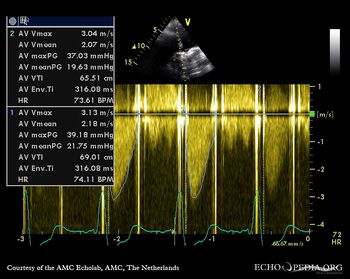

| Continuous-wave Doppler signal of transaortic flow | Pulsed-wave Doppler signal of flow in left ventricle outflow tract |